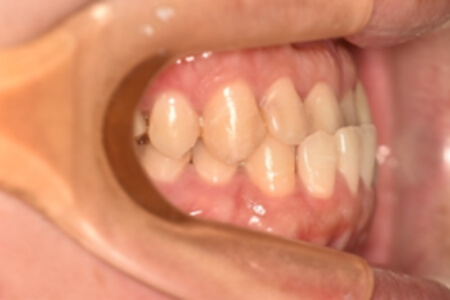

| 治療内容の詳細 | 初診時26歳の男性で、受け口を気にされ来院されました。 検査の結果、下顎前突、上顎前歯部叢生および上顎側切歯反対咬合を伴うアングルⅢ級不正咬合と診断しました。 先ず、前期治療として、リンガルアーチを使用し、上顎中切歯を前方へ移動させ、反対咬合の改善を行いました。 その後、マウスピース型矯正装置(インビザライン)で配列を行いました。 治療期間としては1年8か月でした。 |